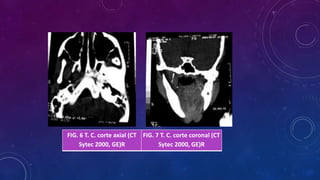

FIG. 6 T. C. corte axial (CT

Sytec 2000, GE)R

FIG. 7 T. C. corte coronal (CT

EXAMENES AUILIARES Visión enmayor aumento del área afectada RADIOGRAFIA PANORAMICA

FIG. 6 T.C. corte axial (CT Sytec 2000, GE)R FIG. 7 T. C. corte coronal (CT Sytec 2000, GE)R